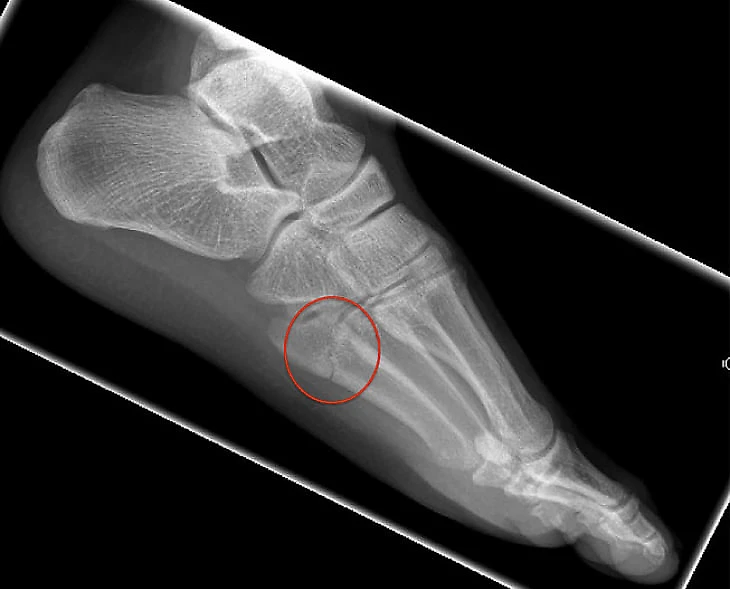

Пятая плюсневая – тонкая кость, которая ведет к мизинцу на ноге. На FIFA Medical Network (сеть для футбольных врачей, создана ФИФА) указано, что ее переломы распространены в футболе. Они вызваны либо ударом по ноге, либо сильным изгибом стопы. Как правило, в футболе перелом происходит в самом основании кости.

«Операция, проведенная доктором Родриго Ласмаром, прошла успешно. Она заключалась во внедрении винта, соединенного с трансплантатом, закрепленном на уровне поражения пятой плюсневой кости», – подробно описывал тогда «ПСЖ».

В официальном сообщении «ПСЖ» назвал эту травму рецидивом старого повреждения, но были и хорошие новости: по данным Globo Esporte, винт, вставленный во время прошлогодней операции, не сместился, это упрощало восстановление. После дальнейших обследований врачи решили, что в новом случае можно обойтись без операции.

Две похожих травмы в одно и то же время сезона вызывают тревогу. В медицине есть понятие стрессовый перелом – когда кость не выдерживает постоянной нагрузки. Но надо уточнить, что никто из окружения Неймара и «ПСЖ» не применял этот термин. «Рецидивы после таких травм встречаются не так часто, – объяснял спортивный врач Хулио Градос в интервью El Comercio. – Во время операции вставляется винт и костный трансплантат, чтобы пятая плюсневая кость не сломалась снова. Но в случае с Неймаром, к сожалению, это повторилось».